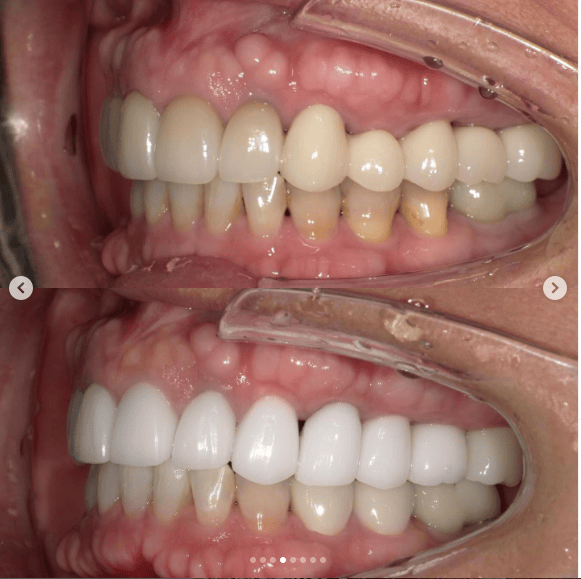

Case022 – インプラント

広島からの患者様です。

前歯を綺麗にしたい。インプラントをしたい。

という主訴で東京の歯医者をいろいろ調べて当院を選んでくださいました。

毎回、遠い中しっかり通ってくださり、選んで頂けた嬉しさと、その気持ちに応えたいという想いで診療させて頂きました。

前歯はご希望のお色でラミネートベニアでは出せない透明感のあるセラミックに上下左側7はインプラントをさせて頂きました。

左上は破折で温存不可。

骨も少なかったので、サイナスリフトも行い計五回の来院で被せ物を入れさせて頂きました。

左下は前回のクリニックでの埋入位置が深すぎて食べカスも毎回詰まる、セルフメンテナンスではら汚れも取れない。インプラント周囲炎にもなっていたので、一度前のインプラントを除去し、そこから新しくインプラントを埋入し、診療させて頂きました。